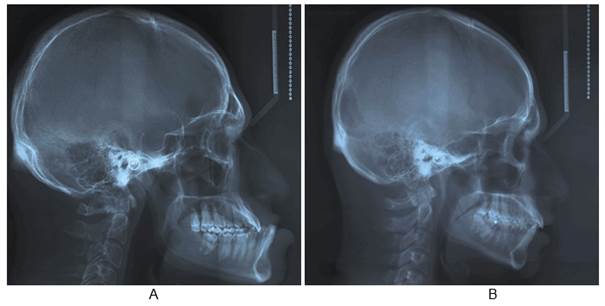

Paciente de 27 años, sexo masculino, fue derivado por Endocrinología con diagnóstico de acromegalia por adenoma de hipófisis al Servicio de Cirugía Máxilo Facial del Hospital San Borja Arriarán en Santiago de Chile para tratamiento correctivo de la deformación facial. En la anamnesis, el paciente relata la existencia de un hermano gemelo. Por esta razón, se les solicitó a ambos hermanos un consentimiento para la realización de este estudio. El hermano gemelo accedió voluntariamente a realizarse un registro telerradiográfico lateral craneofacial. Ambos registros estandarizados se realizaron en las mismas condiciones y con el mismo equipo radiológico (Planmeca Promax).

Obtenidas ambas telerradiografías (Fig. 1), se realizó un análisis cefalométrico con algunas medidas angulares comúnmente utilizadas en ortodoncia 13. Posteriormente se realizaron dos superposiciones cefalométricas: una general y otra mandibular, ambas basadas en el método propuesto por Björk 23-25. Esto permitió visualizar las zonas de mayor cambio morfológico craneofacial del paciente acromegálico respecto de su hermano gemelo.